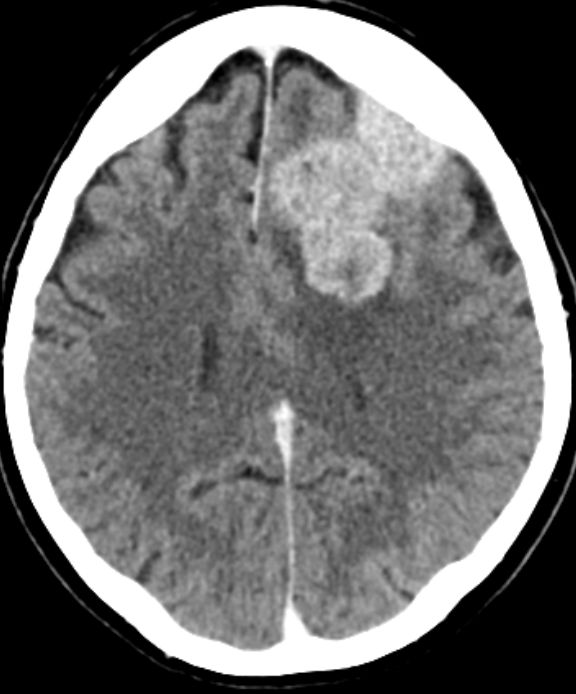

Klinik Scharf begrenzt, homogen, extraaxiale Raumforderung. Breite Verbindung zur Dura. Nach KM homogenes Enhancement. 20% Verkalkungen oder Schädelveränderungen (Hyperostose, Osteolyse). Wenn alle Kriterien erfüllt sind, ist eine histologische Sicherung entbehrlich.

Diagnostik Fallbeispiele

sekretorisches M. seltene, gutartige Sonderform. In 70% starkes perifokales Hirnödem, in 50% hemisphaerisches Hirnödem. Überwiegend ältere Patienten. Typisch basaler Sitz.